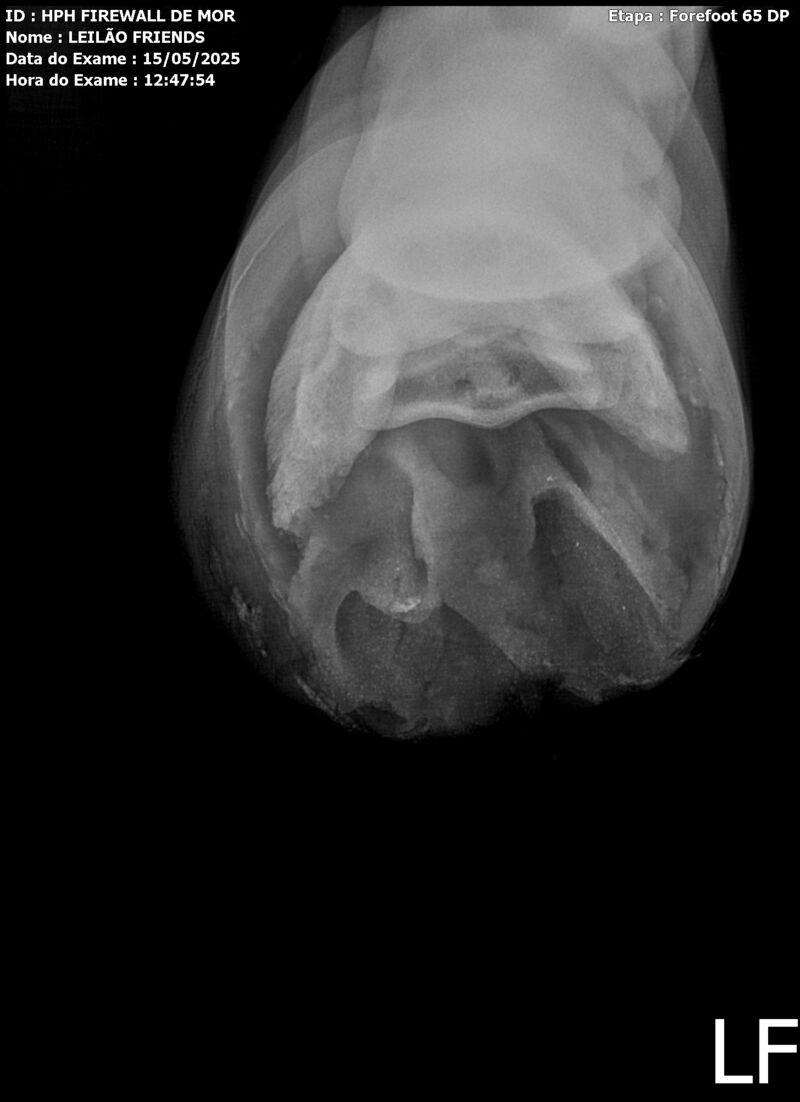

Sexo: MACHO

Nascimento: 13/04/2023

Pelagem: TORDILHA

Altura aproximada: 1,61m

Previsão de altura: 1,66m

Vendedor: HARAS HPH / TRV

Localidade: SÃO PAULO/SP

Garanhão tordilho, apesar de jovem, mostra muito poder e uma plástica de salto incrível. Firewall é sempre muito positivo, busca o salto e os supera com muita agilidade e leveza.